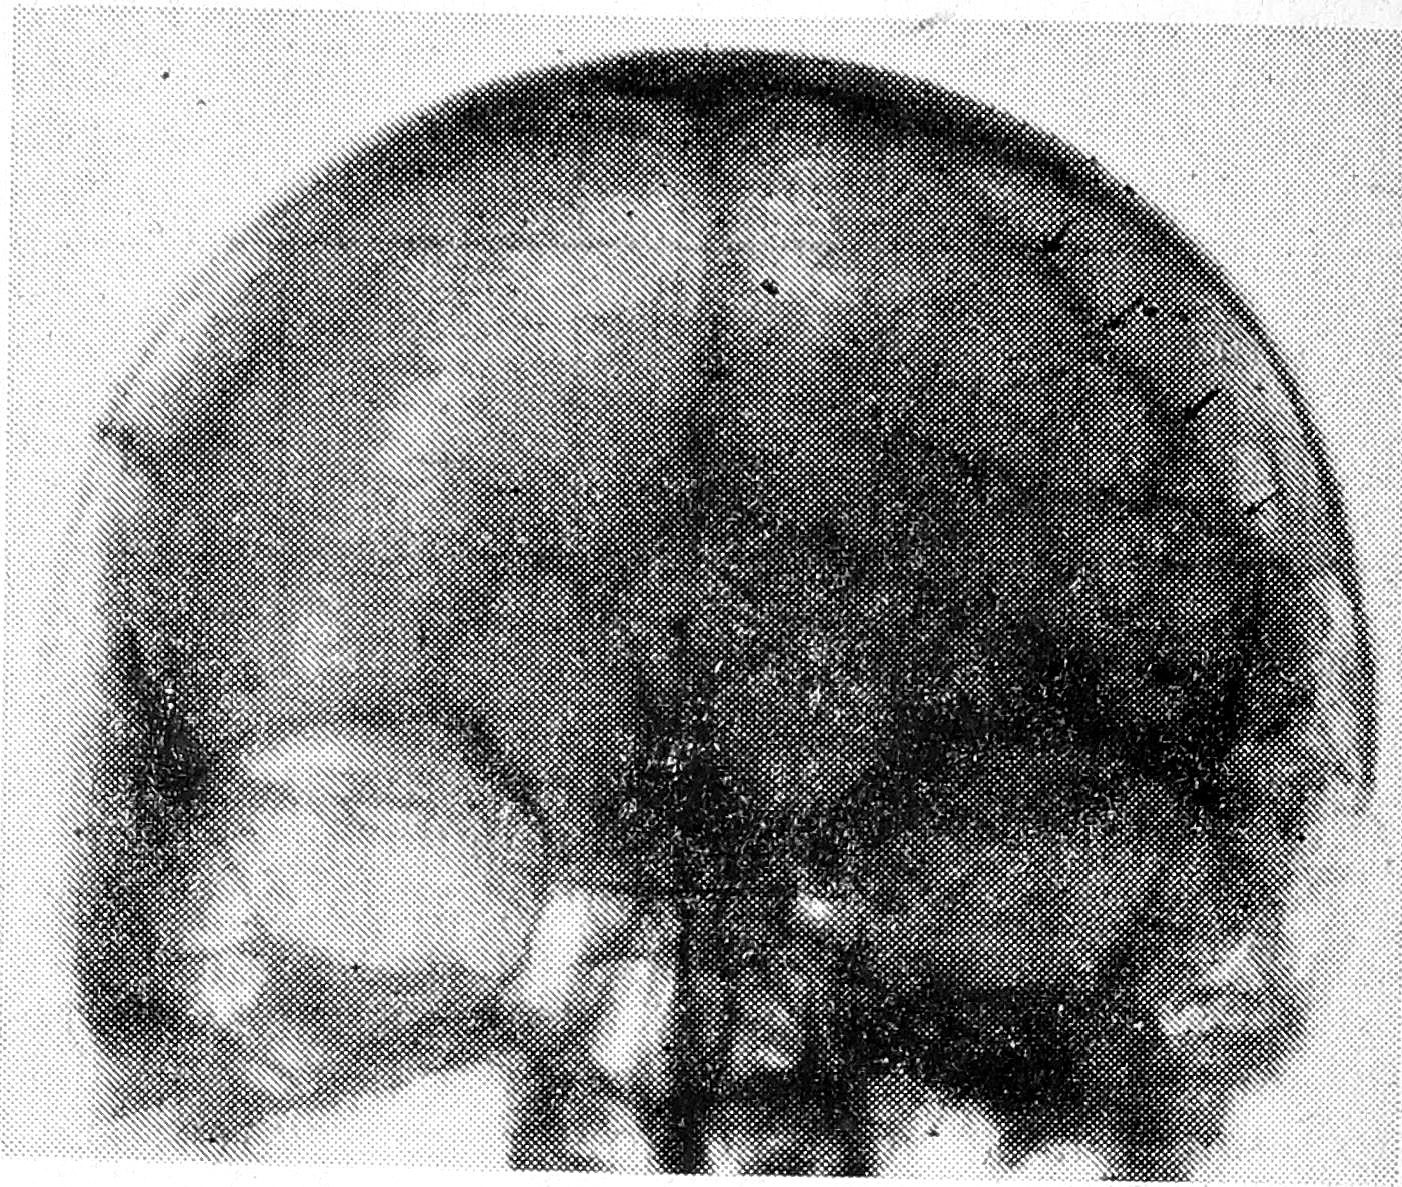

В фазе компенсации наличие хронической субдуральной гематомы может быть установлено с помощью инструментальных методов исследования анатомо-топографического плана, показания к применению которых возникают при установлении в анамнезе факта черепно-мозговой травмы. При одномерной эхоэнцефалографии выявляется смещение М-эхо (рис. 1), при тепловизионном исследовании головы обнаруживается характерный участок повышенного свечения в зоне расположения гематомы (рис. 2). Наличие хронической субдуральной гематомы может быть визуализировано с помощью двухмерной эхоэнцефалографии — по появлению дополнительных сигналов от оттесненных кровью мягких мозговых оболочек и вещества мозга (рис. 3). Диагноз однозначно подтверждается каротидной ангиографией, когда на прямых снимках определяется линзообразная бессосудистая зона с характерным оттеснением сосудов коры мозга (рис. 4).

Рис. 4. Хроническая травматическая субдуральная гематома слева. Каротидная ангиограмма. Оттеснение сосудов коры мозга с образованием аваскулярной зоны.